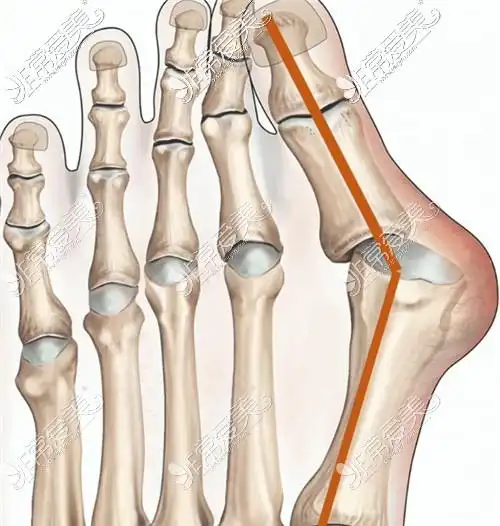

大脚骨病的微创手术

如何正确矫正大脚骨超微创真的这么好吗

拇外翻大脚骨手术矫治术